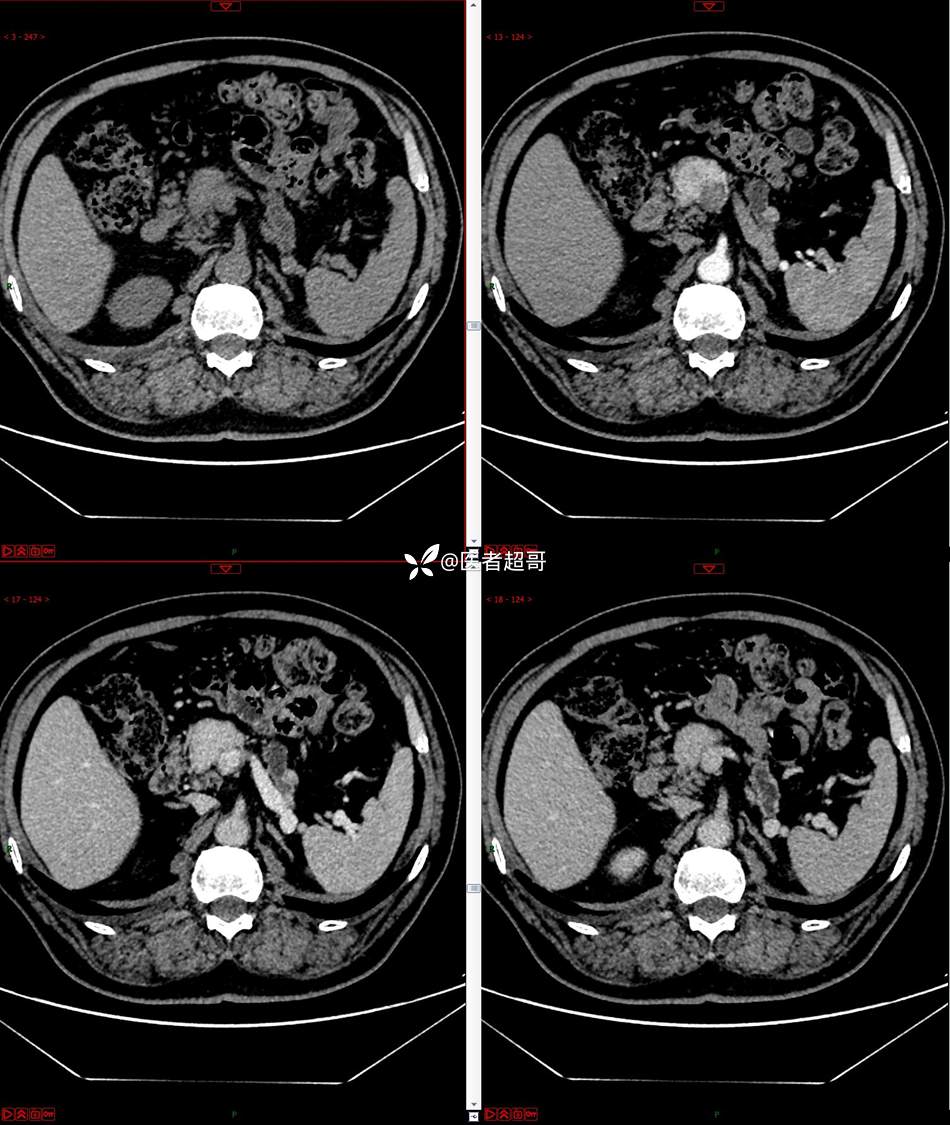

【影诊笔记677】查体发现胰腺占位性病变1周,细节决定成败,请诊断分析!

主 诉:查体发现胰腺占位性病变1周。

现病史:患者1周前在当地查体时发现胰腺占位性病变,无恶心、呕吐,无腹痛,无寒战、高热,无咳嗽、咳痰等异常不适,来我院门诊查上腹部CT平扫+强化:胰腺尾部异常密度灶。今为求进一步治疗,门诊以“胰腺占位性病变”收入院。患者自发病以来,一般情况可,神志清,精神可,普通饮食,二便正常,体重及体力无明显改变。

既往史:既往糖尿病病史2年,口服二甲双胍早晚各一片和格列吡嗪早晚各一片,否认高血压、心脑血管病等疾病史,否认肝炎、结核或其他传染病史及密切接触史,预防接种史不详,否认药物及食物过敏史,否认外伤史,12年前肾癌切除术手术史,否认输血史,其它无特殊。